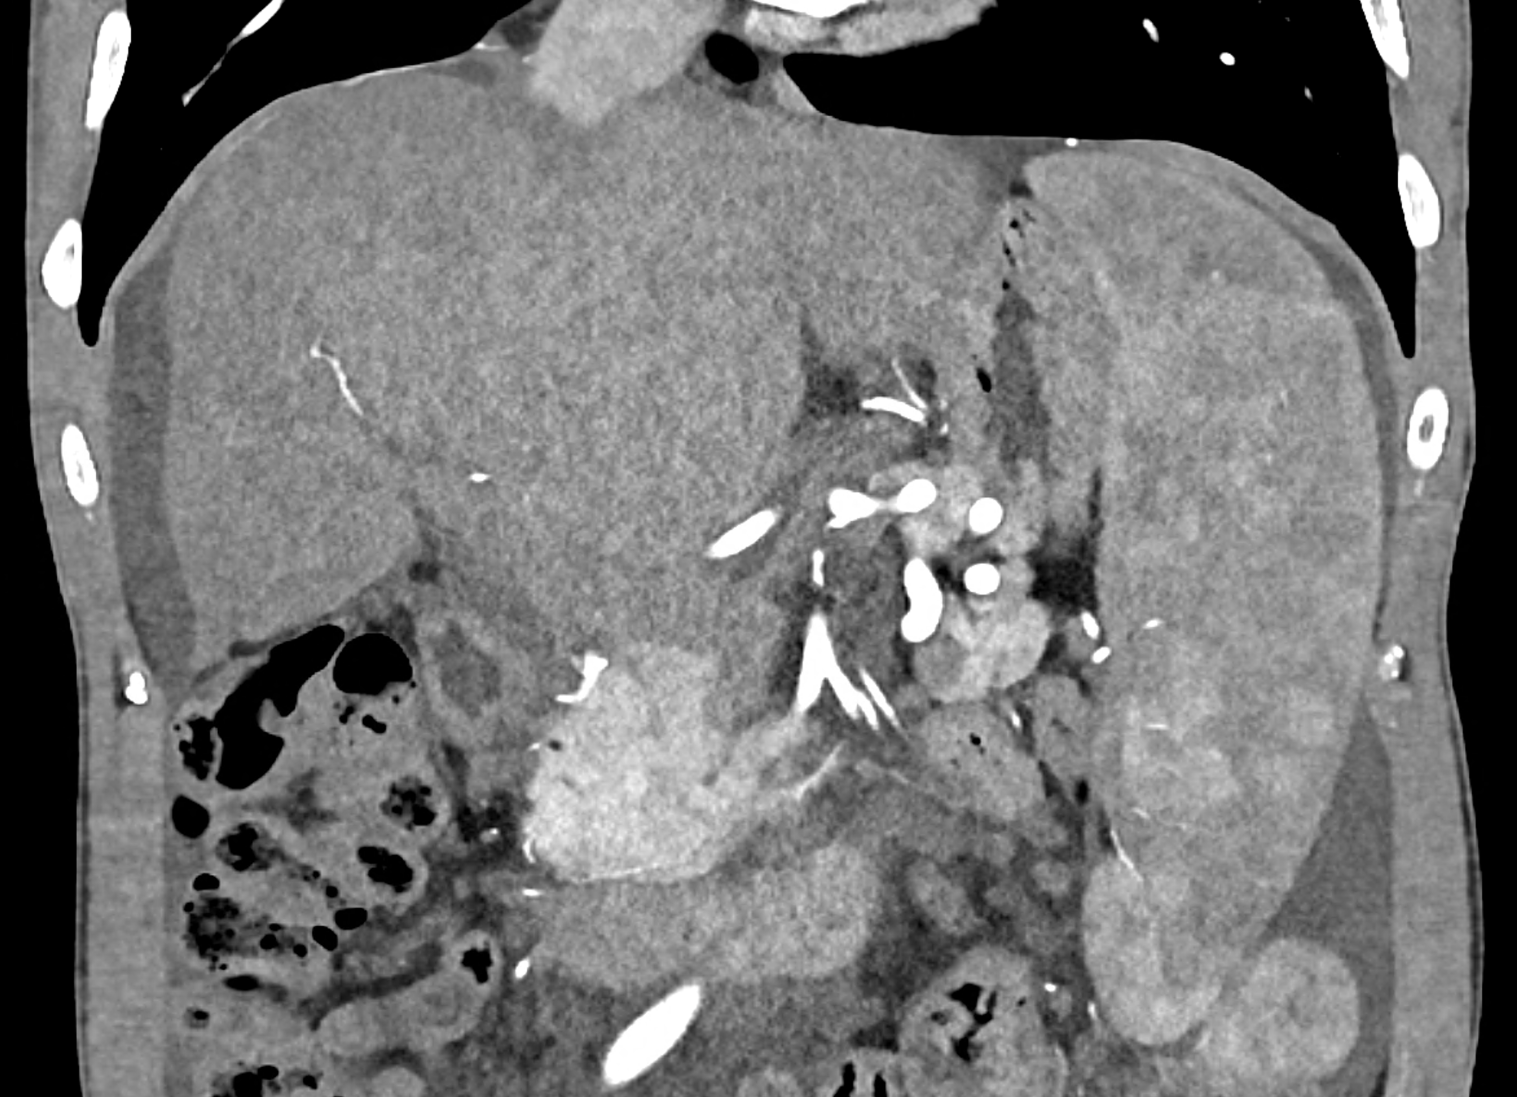

In CT images, BCS manifests as non-homogeneous enhancement of liver tissue in the arterial and especially in the portal phase, although in the portal phase may be increased, especially in the caudate lobe and left lobe, which are often hypertrophic (the hypertrophy and the enhancement is caused due to the possibility of the venous drainage directly into the inferior vena cava through the direct caudate veins), in contrast to the reduction in the right lobe. The portal vein is free, whereas even in the late phase, the hepatic veins and their contrast filling are not visible. Thrombotic occluded veins are hypodense.

A patient in his sixties with a Leiden mutation of factor V and a heterozygous prothrombin mutation presents with abdominal pain. Ultrasound examination reveals ascites and enlargement of the liver.There is enlargement of the liver, particularly the left lobe and caudate lobe. The hepatic veins are centrally filled with contrast medium due to reflux at the confluence with the inferior vena cava, and their radicular parts are thrombosed. There is typical chronic liver remodelling and the formation of centrifugal collateral circulation, including esophageal varices, and ascites is present in the abdominal cavity.

coronary view documenting splenomegaly, different enhancement of the liver parenchyma, and ascites, the arterial, and the portal phases